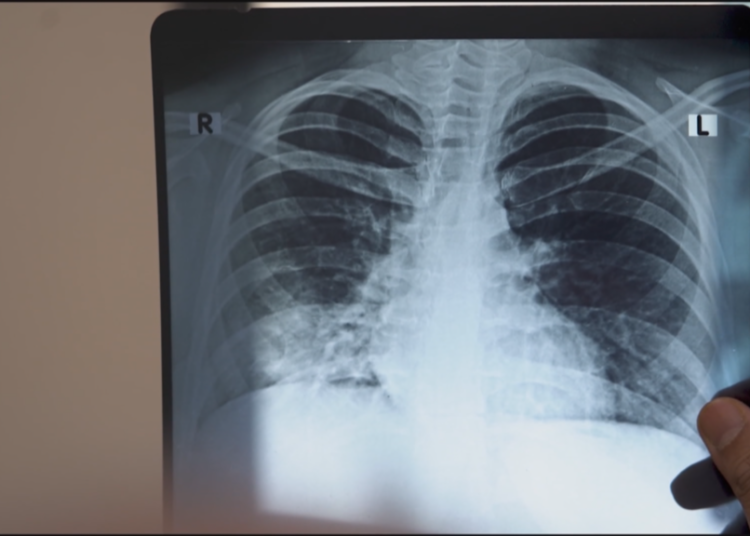

In 2018, Indian Prime Minister Narendra Modi promised to eradicate tuberculosis (TB) within the nation by 2025, aiming to set an instance globally. Since December 2024, India’s well being minister has led a “100-day marketing campaign” to eradicate TB, however current WHO information exhibits India is much from its purpose. It recorded 2.5 to three million new instances and over 400,000 deaths in 2023 alone, accounting for a 3rd of world TB instances and deaths. The nation faces two main points: TB remedy shortages and the rise of multi-drug-resistant TB. Whereas remedies exist, the federal government’s gradual approval of their distribution has hindered progress, leaving India at a crucial juncture in its combat towards the illness. FRANCE 24’s Khansa Juned and Alban Alvarez report.